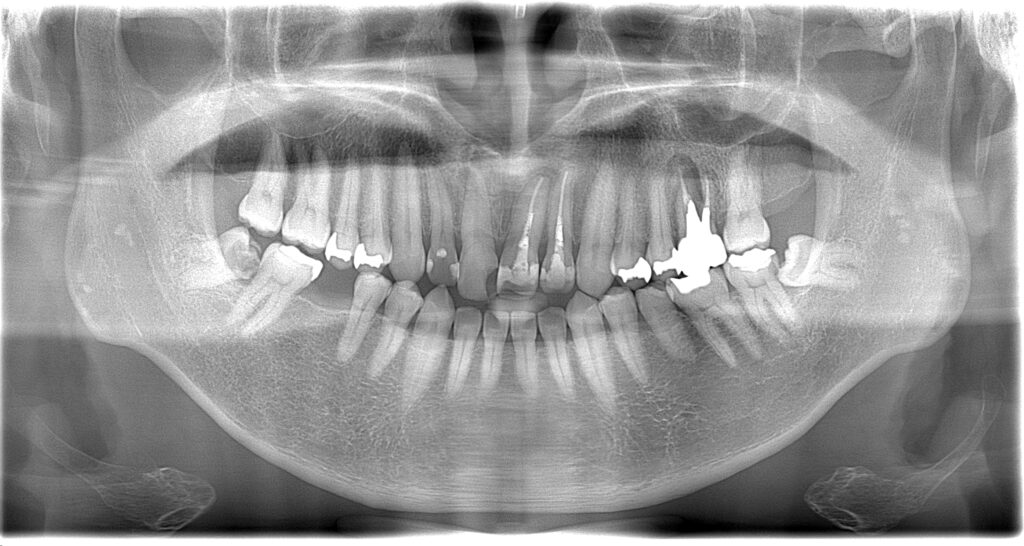

こんにちは。今日は銀の詰め物取れた方が来られました。詰め物はなくして少ししみるという事でした。

昔は歯の噛む面の虫歯も銀歯で修復している事が多かったですが、今は小さな範囲は白い修復物で仕上げる事が一般的です。